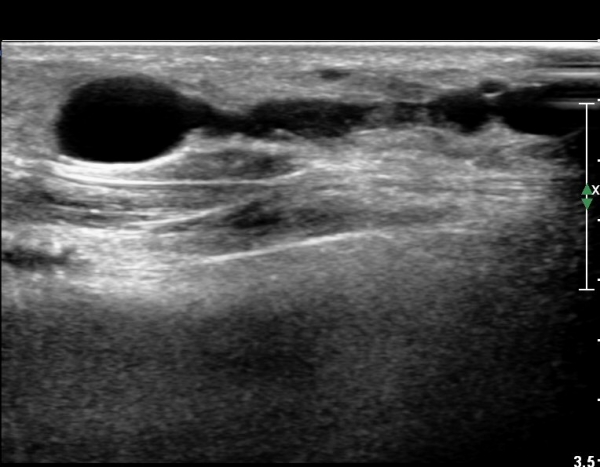

¾ÕÂÊ ¸»´Ü °æ°ñºñ°ñ°üÀý ¾à 5cm ±ÙÀ§ºÎ Ⱦ´Ü몀°Ë»ç ½Ã õºñ°ñ½Å°æ Àü¸é¿¡ Àú¿¡ÄÚ ³¶Á¾¿¡ ÀÇÇÑ ½Å°æ ¾Ð¹ÚÀÌ °üÂûµÈ´Ù(ÀÌ °üÂûµÈ´Ù(»çÁø 6, 7).

¸»´ÜÀ¸·Î °¥ ¼ö ·Ï ³¶Á¾ÀÌ Ä¿Áø°í õºñ°ñ½Å°æ ¾Ð¹ÚÀº ½ÉÇØÁø´Ù(»çÁø 8).

³¶Á¾À» Á¾´Ü¸éÀ¸·Î °üÂûÇÏ´Ï ³¶Á¾ÀÌ ¸»´Ü °æ°ñºñ°ñ°üÀý¿¡¼ À¯·¡µÊÀÌ È®ÀεȴÙ(»çÁø 9).